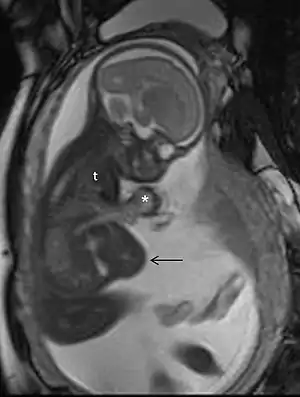

| MRI in pregnancy in a case of pentalogy of Cantrell, showing ectopia cordis (*), partial herniation of the liver (arrow), and a small thoracic cavity (t) | |